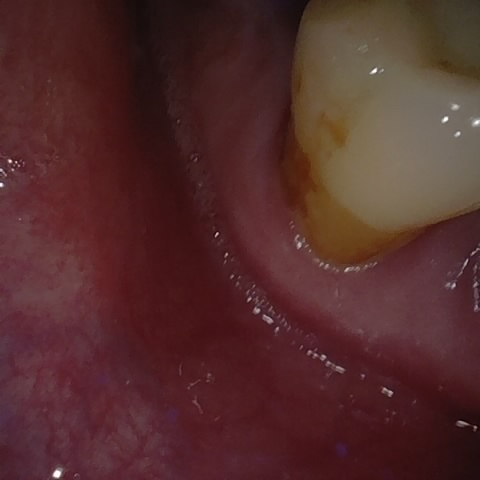

Annotated as "Good"